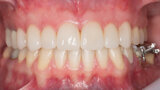

Fig. 25: Final results of the analogue and digital approach.

Fig. 26: Final results of the analogue and digital approach.

Fig. 27: Final results of the analogue and digital approach.

Fig. 28: Final results of the analogue and digital approach.

Fig. 29: Final results of the analogue and digital approach.

Fig. 30: Final results of the analogue and digital approach.

Fig. 31: Final results of the analogue and digital approach.